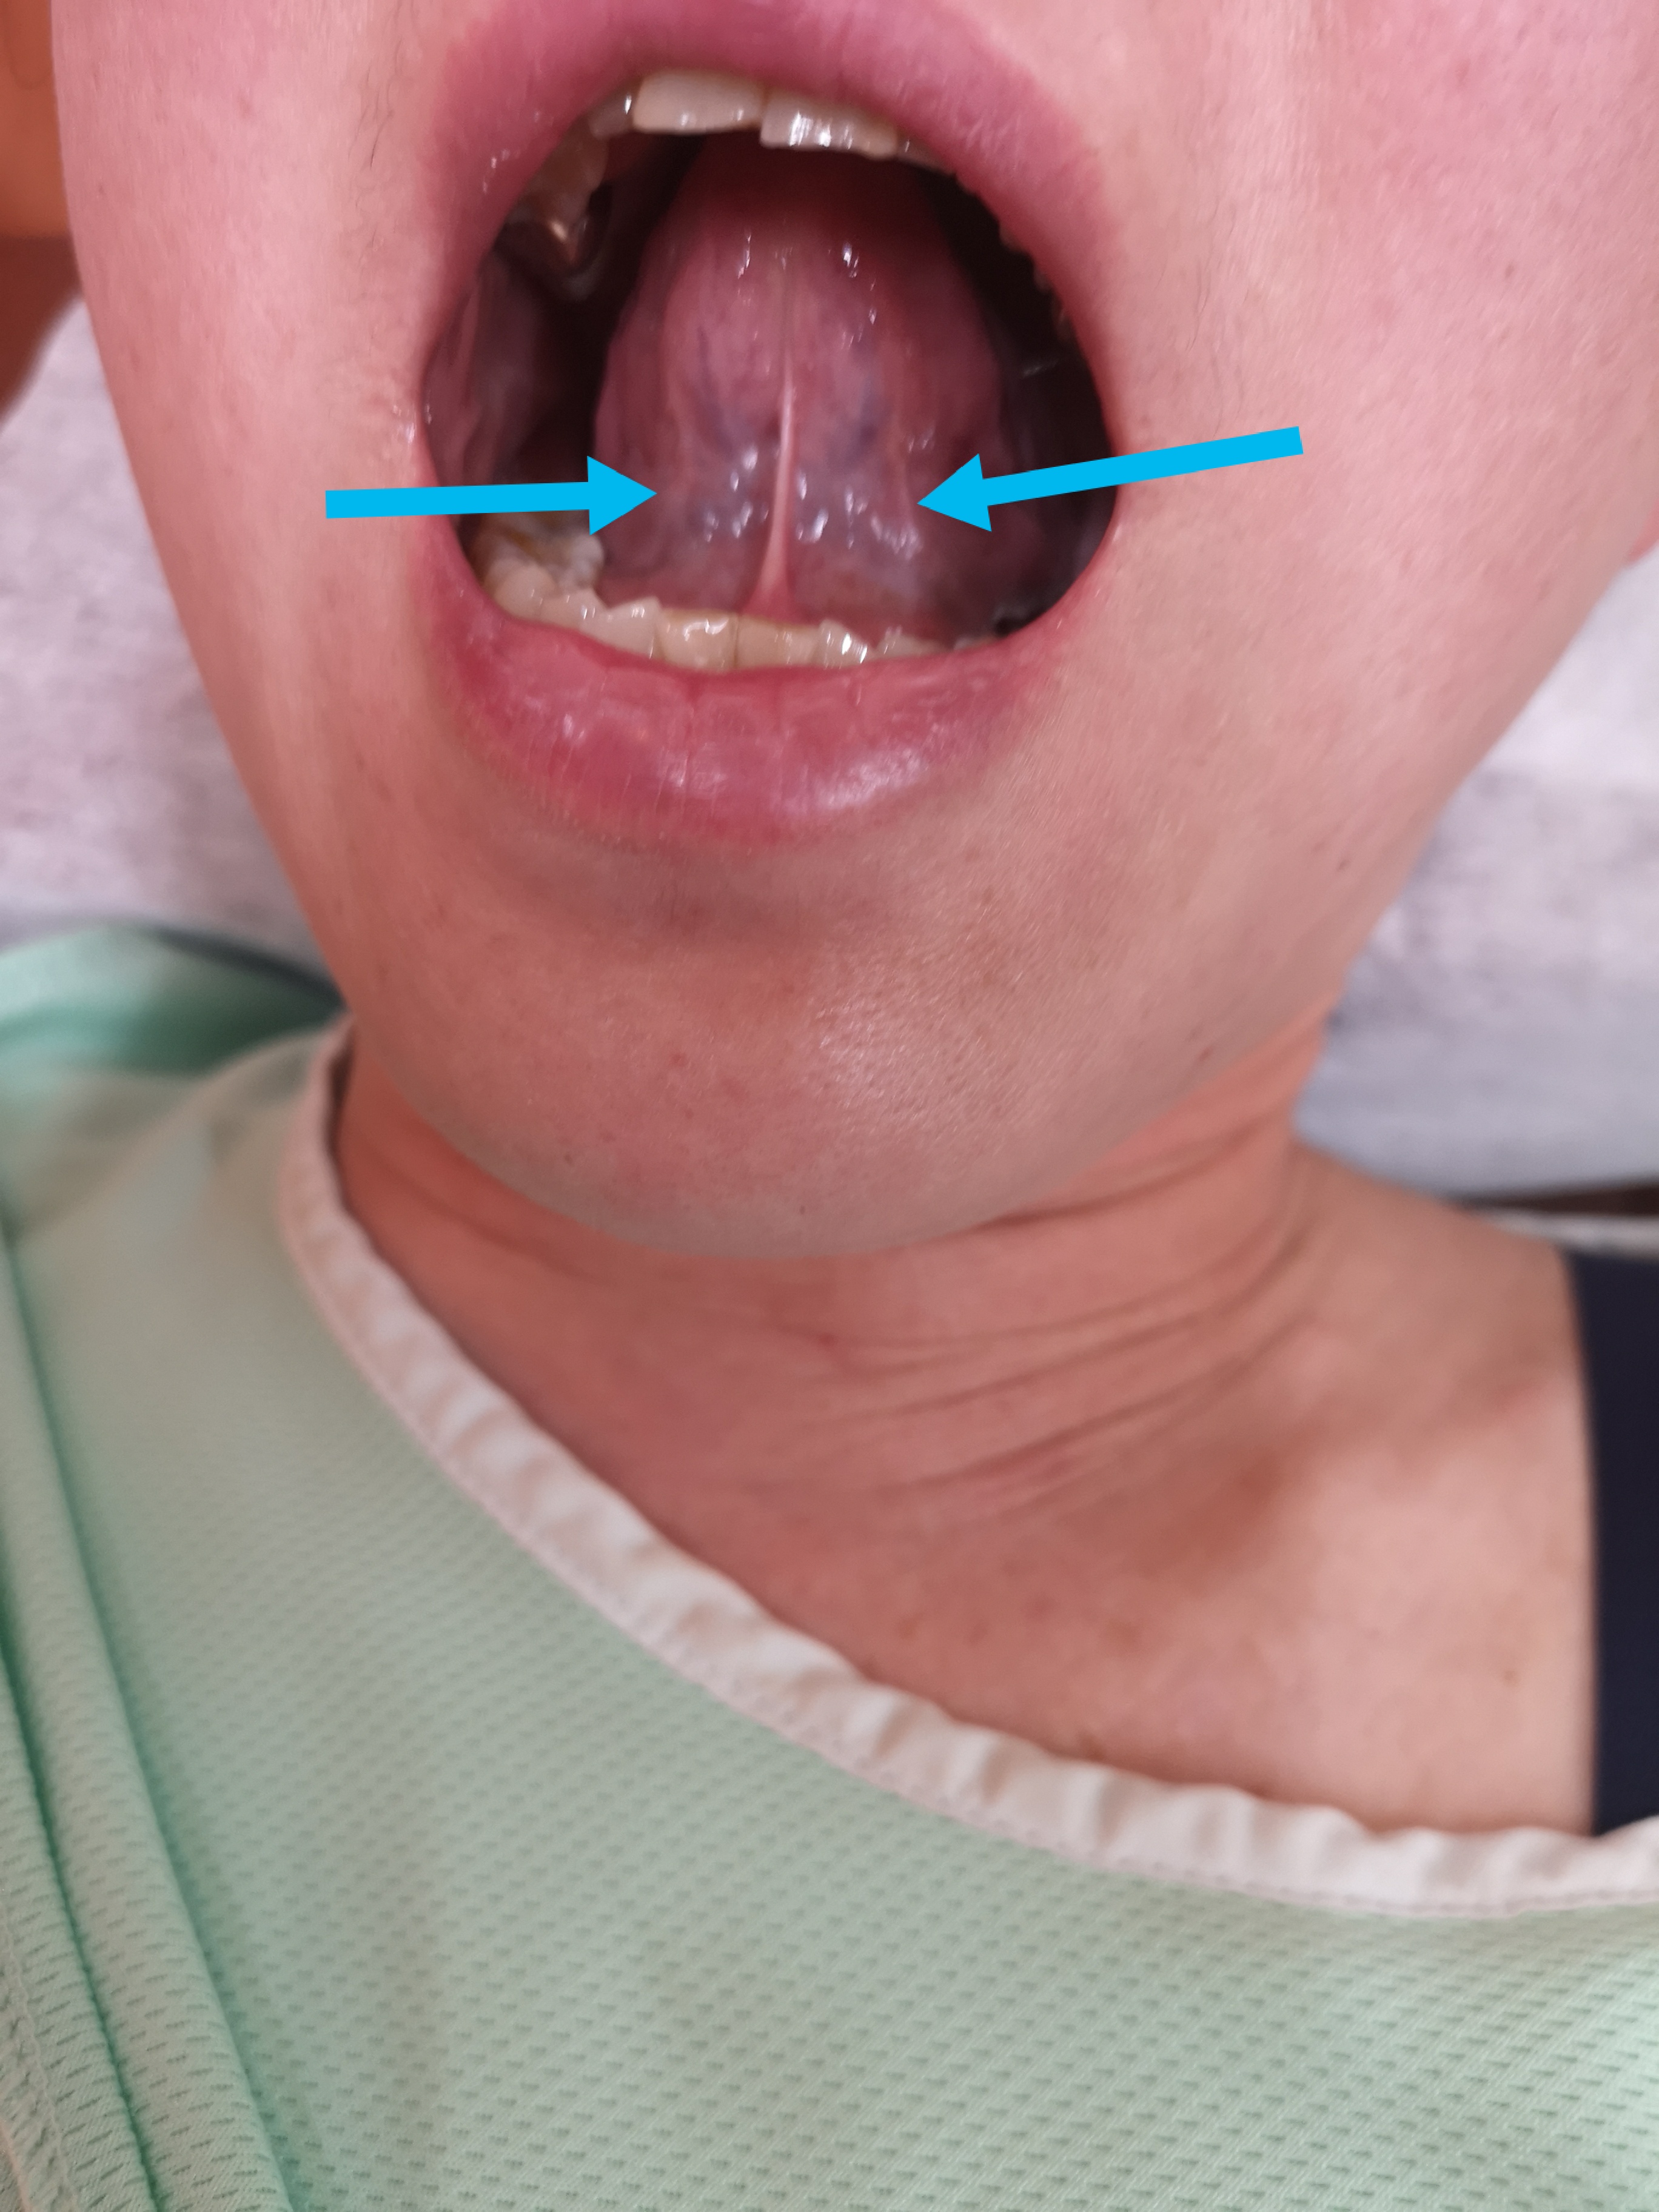

施術後の舌の状態がこちら

怒張が緩和され邪気の勢いが減りました。全身は脳の出先機関であり、全身と脳はお互いに牽制、扶助する

関係です。体に血瘀が溜まると脳がそれを記憶してしまいなかなか痛みが緩和されない事もあります。